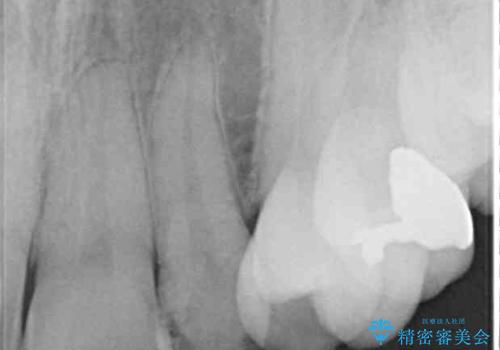

- 結婚式に向けて、八重歯と虫歯で変色した歯を改善したいとのことで来院された患者様です。

上下ともにデコボコが強いため、上下顎左右小臼歯各1歯を抜歯して歯列を整えることとしました。

大きな虫歯が認められた歯は、矯正治療後にオールセラミッククラウンにて補綴治療を行うこととしました。